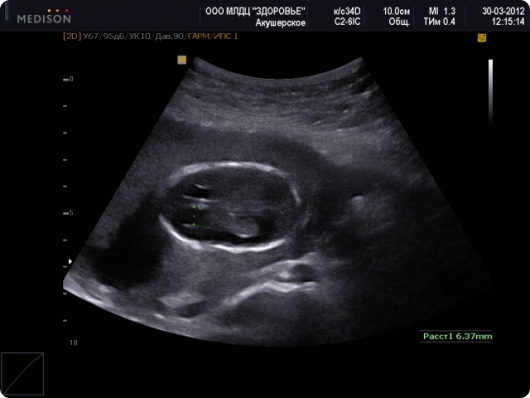

Маловоддя при вагітності зустрічається приблизно у 5 з 100 жінок. Причому виявляється воно як у первісток, так і повторнородящих незалежно від віку. Даний діагноз ставиться на підставі результатів УЗД , За якими вираховується індекс амніотичної рідини (ІАЖ):

ІАЖ діагноз 5-8 см норма 2-5 см помірне маловоддя менш 2см виражене маловоддя

Як бачимо в залежності від індексу АЖ, лікар може поставити один з двох діагнозів: помірне маловоддя або виражене маловоддя. І в тому і в іншому випадку вагітної є над чим задуматися, так дана патологія може стати причиною проблем у дитини в подальшому. У всіх випадках маловоддя викликає внутрішньоутробну затримку розвитку плода, так як він змушений розвиватися в умовах нестачі кисню і поживних речовин.